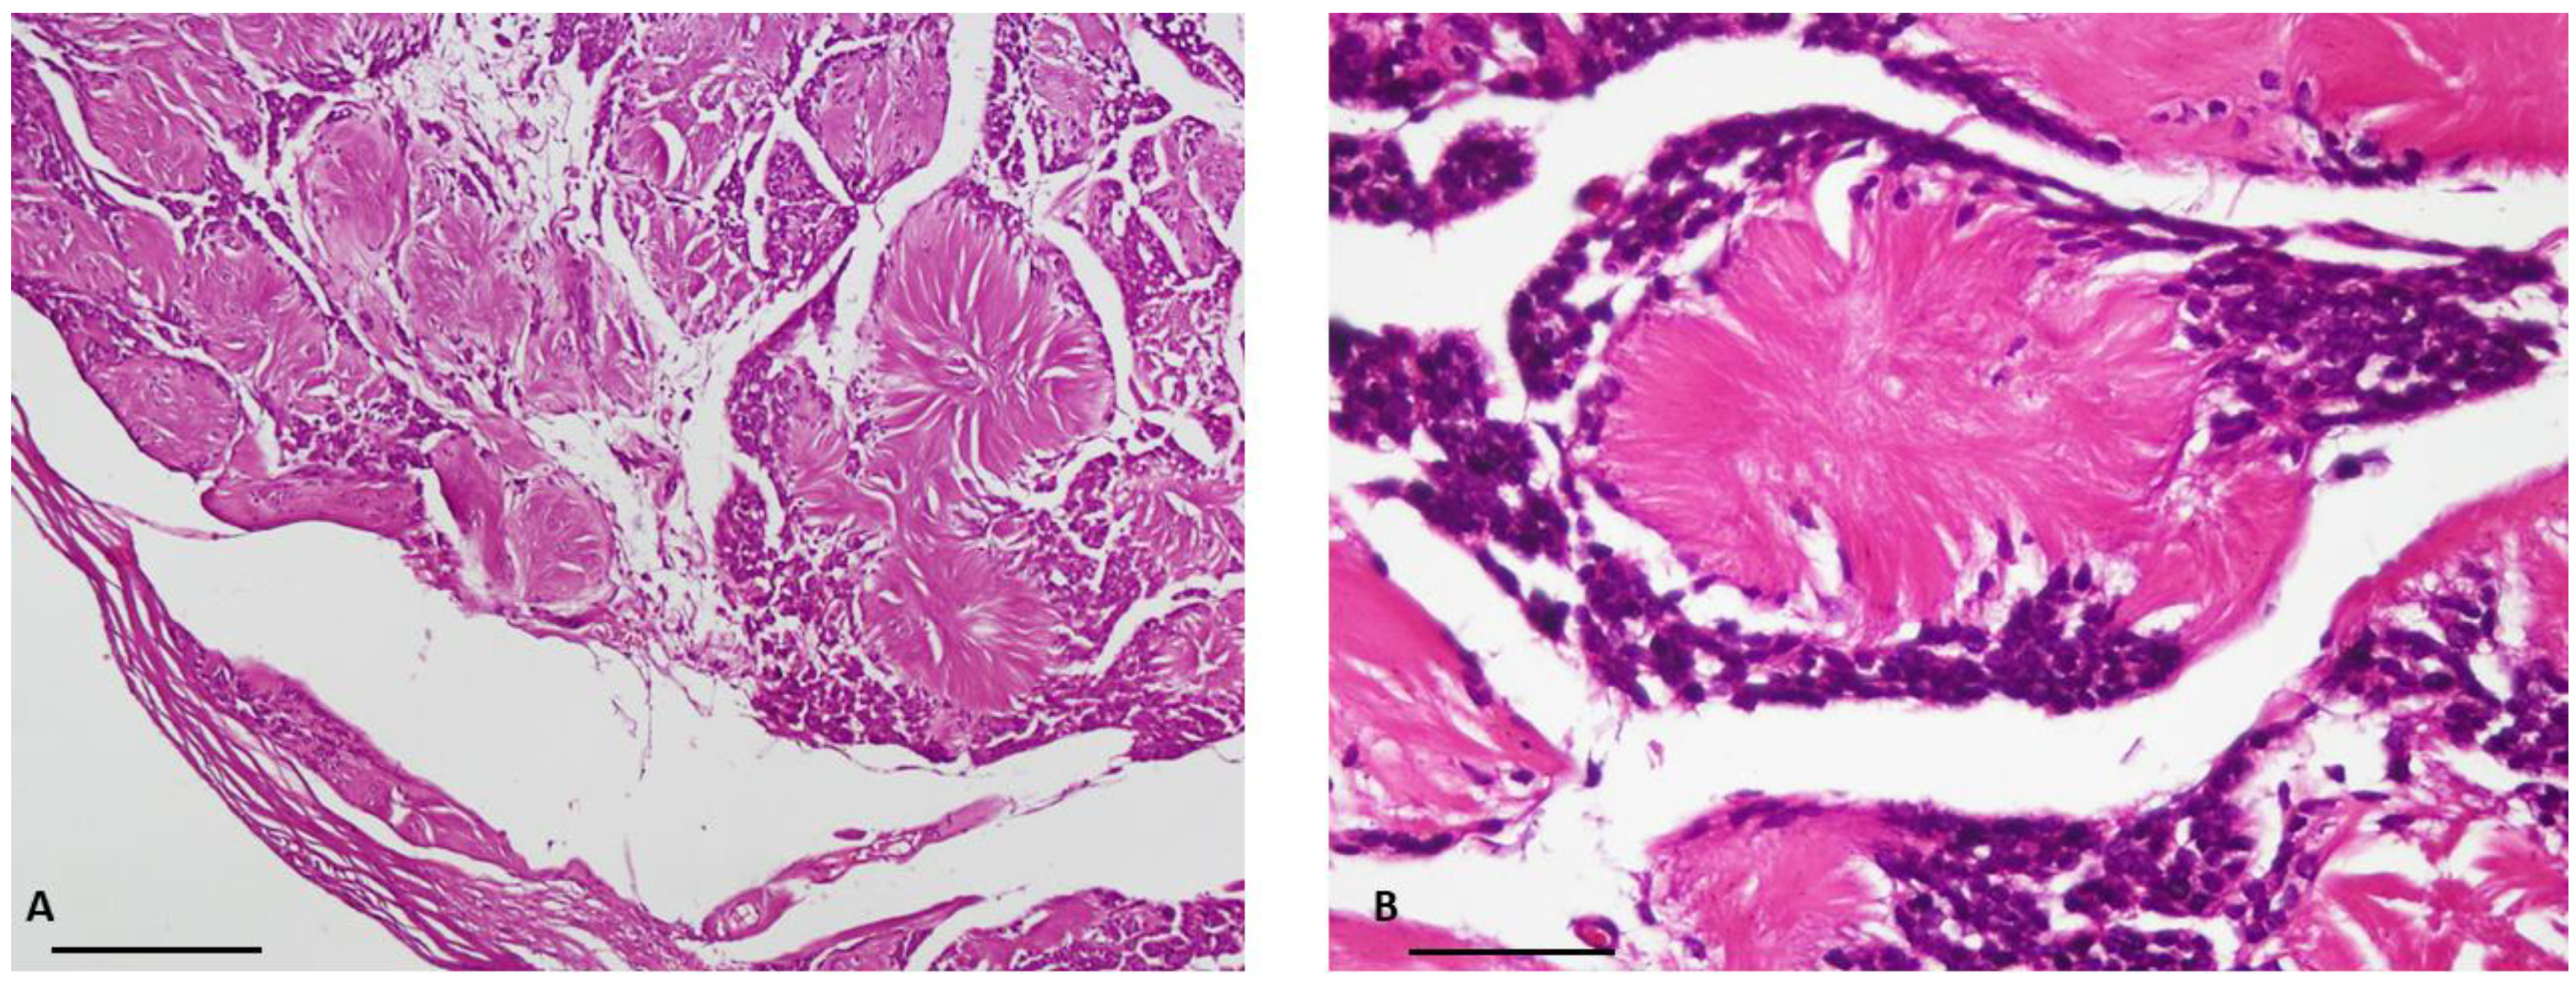

Figure 3. Immunohistochemical profile of neuroblastoma-like schwannoma (10× objective lens): (A) Schwann cells show strong and diffuse positivity for S100 marker; (B) Tumor cells are focally stained by Neuron Specific Enolase (scale bar = 100 μm).

Masson’s trichrome staining confirmed that the central core of the rosettes was composed of collagen fibers. Subsequent immunohistochemical study revealed diffuse expression of S100 protein (as the most commonly used marker to detect tumoral cells) [6] in the tumoral cells, confirming the Schwann cell origin of the tumor (Figure 1 and Figure 2). Additionally, staining for the neural markers showed focal positive expression for Neuron Specific Enolase (NSE) and negative for synaptophysin which confirmed our diagnosis (Figure 3 and Figure 4).

Immunohistochemical methods helped us to reach a definite diagnosis. Indeed, in our case, the tumor cells were strongly and diffusely positive for S100 protein and focally positive for NSE. Neuroblastoma-like schwannoma showed focal areas with typical immunophenotyping of conventional schwannoma and all tumor cells were strongly and diffusely positive for S100 protein, but typically negative for other markers of neural differentiation, such as synaptophysin [3]. However, there are reports in which the tumor cells show positivity for other neural markers such as NSE [9].